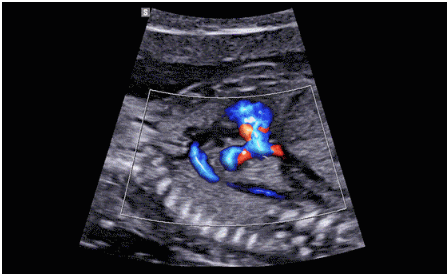

CrystalLive?是三星最新的超聲成像引擎,同時增強(qiáng)了2D圖像處理能力、3D渲染能力和彩色信號處理能力,能夠在復(fù)雜情況下提供出色的圖像性能,具備檢測外周血管、微循環(huán)血流的能力。